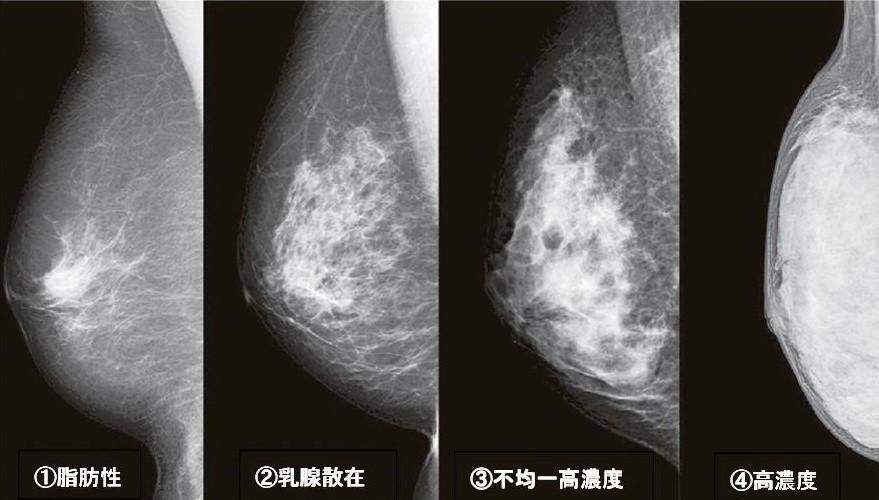

マンモグラフィでは、乳腺実質と脂肪の量から、写真画像のように4種類に分類されます

(1)脂肪性

乳腺内がほとんど脂肪に置換しているため、マンモグラフィでは乳房のほぼ全体が黒く写ります

(2)乳腺散在

乳腺内の脂肪が70~90%程度で、マンモグラフィでは黒い部分と白い部分が混じっていますが、黒い部分が多く写ります

(3)不均一高濃度

乳線内の脂肪が40~50%程度で、マンモグラフィでは黒い部分と白い部分が混じっていますが、白い部分が多く写ります

(4)高濃度

乳腺内の脂肪が10~20%程度で、マンモグラフィでは乳房のほぼ全体が白く写ります